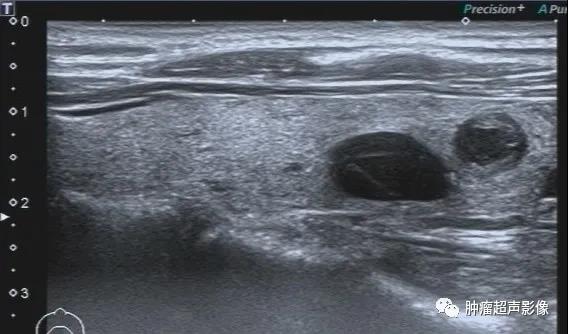

甲状腺下极结节,病史不明,呈低回声,边缘光整,呈双环征(周边低回声晕),内部无血流,采用超微血流成像显示内部无血流,呈“黑洞征”,从而增加诊断皱缩结节的信心,避免穿刺及手术。